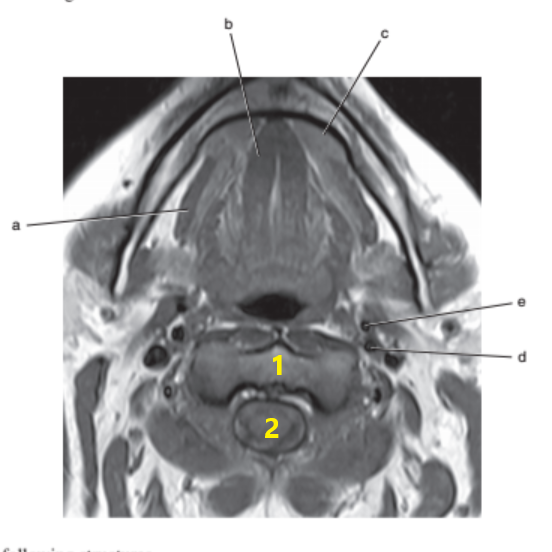

Thyroid gland

What is # 1 ?

Tongue

Epiglottis

What is # 3 ?

Brain stem